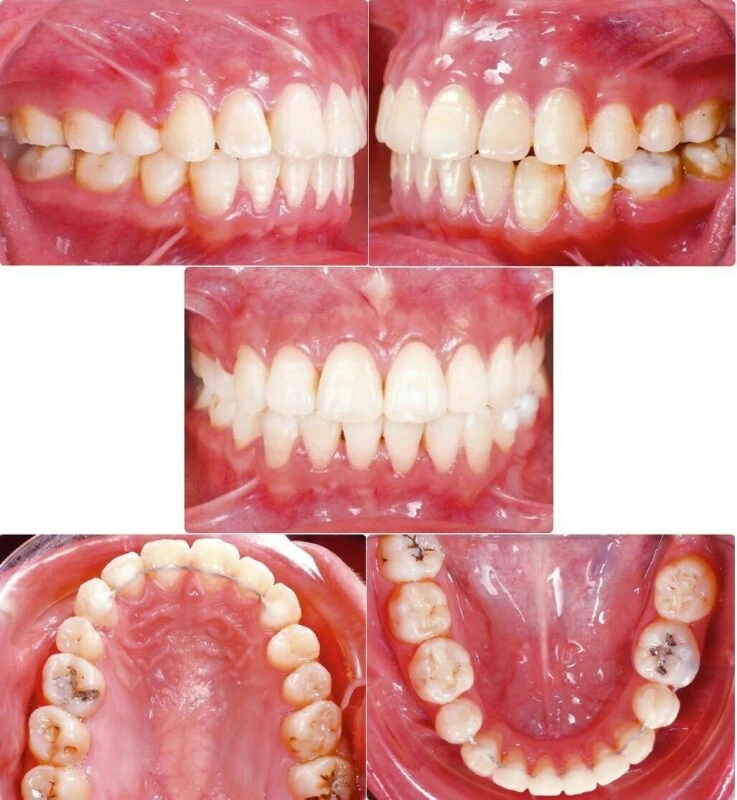

Mặc dù các vấn đề nội nha và mong muốn không sử dụng minivis đã đặt ra một thách thức lớn, nhưng quá trình điều trị vẫn hoàn thành và đạt được sự hài lòng của bệnh nhân (Hình 4-8). Báo cáo này sẽ phân tích chẩn đoán, kế hoạch điều trị và cơ chế đặc biệt để đạt được kết quả điều trị tốt với các vấn đề khó khăn của bệnh nhân.

Hình 5 Ảnh chụp trong miệng sau điều trị

Hình 6 Mẫu nghiên cứu sau điều trị

Thẩm mỹ khuôn mặt đã được cải thiện đáng kể. Vẩu xương ổ răng đã giảm nhiều dẫn đến cơ cằm bớt căng khi khép môi. Các thay đổi này đã cải thiện hình chiếu của cằm và mũi, dẫn tới cải thiện nét mặt nghiêng của bệnh nhân. Nếu sử dụng minivis thì đã kéo lùi được nhiều hơn nữa và việc đóng 13 mm khoảng nhổ răng hàm dưới không đối xứng đã dễ hơn rất nhiều. Tuy nhiên, đã đạt được mục tiêu điều trị với sự hài lòng của bệnh nhân mà không cần sử dụng bất kỳ hình thức neo giữ xương nào, nhưng quá trình tinh chỉnh cuối cùng chưa thực sự kỹ lưỡng do bệnh nhân phải đi Úc. Các ảnh chụp trong miệng và mẫu nghiên cứu sau điều trị cho thấy tương quan răng nanh và răng hàm lớn Loại I ở bên phải, và tương quan răng hàm lớn Loại III và răng nanh Loại I ở bên trái. Đường giữa cung răng dưới lệch 1 mm sang trái so với đường giữa cung răng trên.